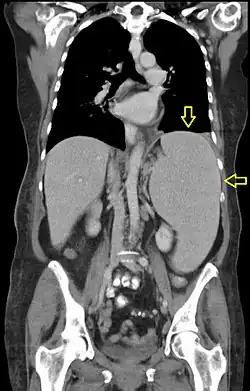

Se denomina hepatoesplenomegalia al aumento simultáneo objetivable del tamaño del hígado y del bazo. Este crecimiento del hígado y bazo puede ocurrir por un problema heredado en el cual el hígado no puede procesar el glucocerebrósido. La acumulación de dicha sustancia en los tejidos del cuerpo puede causar un daño grave al sistema nervioso central de los niños pequeños. Esta afección se da en la conocida enfermedad de glucogenosis de tipo IV, dándose, por efecto de la enzima ramificadora. También se produce hepatoesplenomegalia en la enfermedad conocida como mucopolisacaridosis (MPS).

La hepatoesplenomegalia es un signo clínico que contribuye al diagnóstico de varias enfermedades. Aunque suele ser lo habitual, no siempre tienen la misma causa, pudiendo ocurrir que la hepatomegalia y la esplenomegalia tengan un origen patológico diferente.